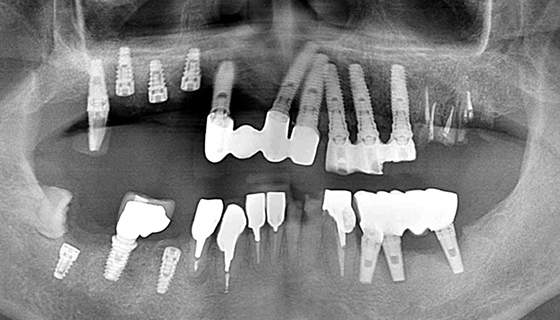

治療前の状態

糖尿病で内科に通院しており、なおかつ喫煙を止めることが出来ない患者さんです。インプラントにとって、糖尿病と喫煙習慣は大敵です。レントゲンを見ても、状態の良い歯はありません。